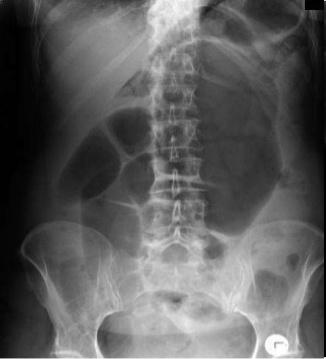

Images hydro-aeriques

d'une occlusion du colon . Ce qui situe

souvent peripherique de l'abdomen et plus hautes que

larges . Cliche ASP expose en debout |

Image hydro-aerique distendue

d'une occlusion du colon . Sa hauteur est souvent

plus que sa largeur et en peripherique de l'abdomen

. |

L'occlusion du colon .

Image hydro-aerique se situe en peripherique du

colon |